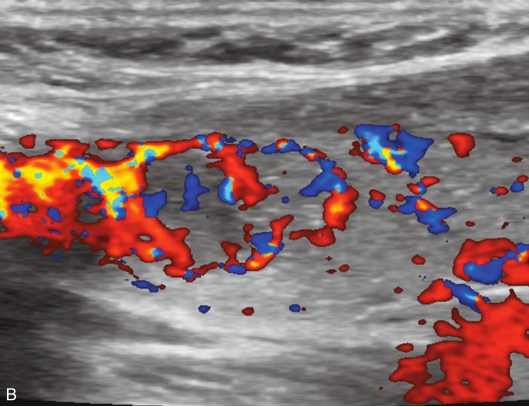

甲状腺左叶中下部见一混合回声结节,边界清,形态规则,中心部可见斑状强回声,CDFI显示周边可见环状血流信号,其内可见丰富血流信号,见图1-3-18。

该结节早于周围腺体组织增强,结节内部呈高增强表现,可见部分无增强区;结节晚于周围腺体组织消退,仍呈高增强表现;结节周边可见均匀高增强环,甲状腺被膜未见明显中断,见图1-3-19、ER1-3-9。

(1)结节增强早期早于腺体增强或与腺体同步增强,增强晚期晚于腺体消退或与腺体同步消退。

(2)结节内部呈均匀或不均匀弥漫性等增强或高增强,增强水平通常高于周围腺体。

(3)结节与周围腺体分界清晰,形态较规则。

(4)部分结节周边可见均匀高增强环。

(5)结节周边被膜连续完整。

甲状腺滤泡性腺瘤通常为富血供病灶,其增强水平等于或高于周围腺体,并呈现“早增强,晚消退”的特点,重点需要与滤泡性腺癌鉴别,腺瘤多边界清晰、形态较规则,造影时结节周围的高增强环厚薄一致、较为均匀,结节周边被膜连续完整、无浸润表现,颈部淋巴结无异常肿大等。而滤泡性腺癌边界不清、呈浸润性生长表现,周边高增强环消失或厚薄不均,如发现颈部异常肿大淋巴结及被膜连续性中断等,需要高度警惕甲状腺恶性肿瘤。

图1-3-18 甲状腺滤泡性腺瘤常规超声声像图

A.甲状腺左叶纵切面超声图像;B.结节内部点状及斑状强回声;C.CDFI血流图

图1-3-19 甲状腺滤泡性腺瘤超声造影图

A.注入造影剂后9s;B.注入造影剂后11s;C.注入造影剂后16s;D.注入造影剂后27s